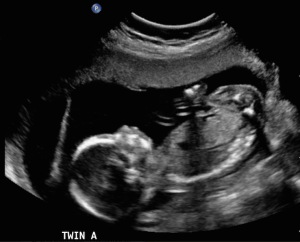

After the exam portion was all complete the tech went out to the second waiting room and brought Steve in, motioned to the end of the bed and said “stand down there I’ll turn the screen so you both can see!” The screen rotated and after more goo the magic wand produced a picture on the screen that we could now both see clearly, hmmm, I don’t see a baby; although early I was expecting a little more of something. I just didn’t remember human anatomy enough to figure out why there was three black spots… the tech pointed to one of the black spots, “the bladder,” showing how truly full it was. “Now what do you see?” the tech said.

“Oh my, there are two” I managed to get out before my jaw dropped too wide to speak. The Tech nodded and I felt Steve’s hands tightened around my feet, I looked down to him, barely able to see through my joy filling eyes; he stood holding my feet in complete awe of what he was seeing on the screen. We stared at the monitor for what felt like a lifetime in complete shock and awe. Finally the tech took the wand away and the screen faded back to a black pictureless monitor. The tech left and I stood wiping the goo away from my abdomen, after I was goo free I looked up at Steve, tears now streaming down my face in total elation and we just stood holding each other amazed at the journey we were about to embark on, this was so much more than either of us had hoped or dreamed of and we were both immediately more than ready for this new life adventure.

With each test and appointment I know that we are one step closer to having the babies. We have been so lucky that Dr. D has an ultrasound machine right in her office so at each appointment we get a glimpse of the babies’ growth and development and the joy of hearing their heartbeats! Getting to see them on the screen so often has been such a wonderful experience!

Steve headed off to the city to finish his final year of trade’s school at the beginning of May; he would be away for two months. As there were appointments that were booked for while he was away my mom and my mother-in-law were able to attend the ultrasounds with me, which helped ease my nerves as well as increase their excitement in the process as they were able to see the two new grand-babies on screen in real time. Steve was able to make it home all but one of the weekends – of which he stayed in the city to study for the final exams. On the weekends he returned home there was much progress with the babies, they began moving and he was able to start feeling them too. Feeling the babies’ move on the outside was good for me too, I felt a little less like I was mistaking gas for movement; which I am sure I did for quite a while! I was able to send Steve pictures and videos from the ultrasounds and of my tummy moving while he was away so he was able to keep up with what was going on for our babies too.